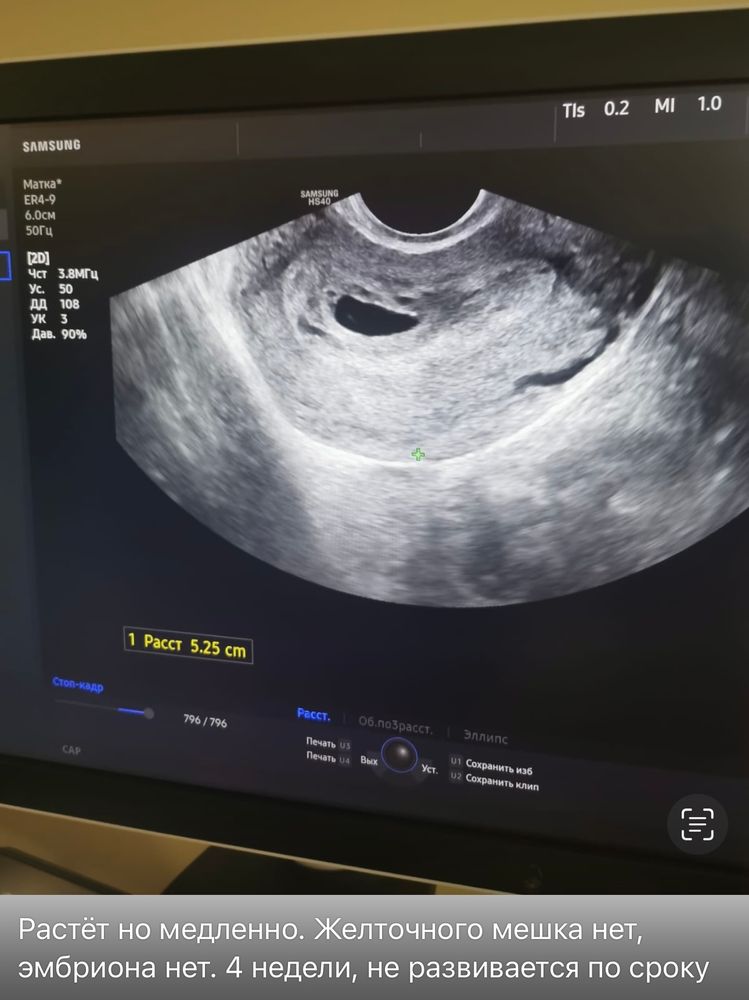

Отсутствие желточного мешка и эмбриона

сделали узи… а, календарь Flo показывал 5н2д… на узи не видно ни желточного мешочка, ни эмбриона. Поставили срок по узи 3-4 недели. Неразбивающаяся под вопросом….

Юлия Медведева, у вас и размер плодного яйца 12мм, а у меня был только 4.2. Так что все будет хорошо, не переживайте) как сказала узист, чаще всего обычные аппараты узи видят эмбрион при размере ПЯ от 17мм

размер плодного яйца 12 мм